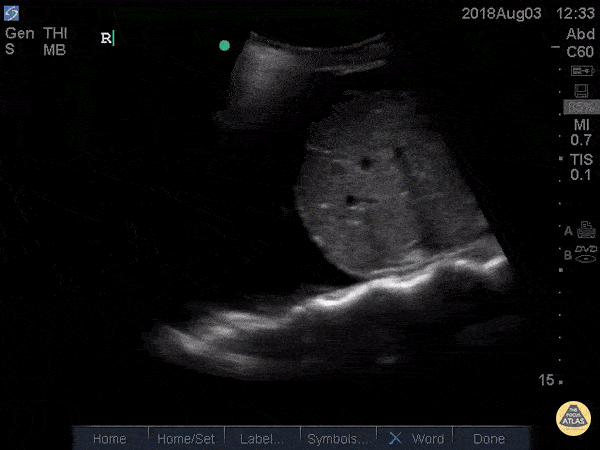

Pulmonary - Spine Sign

41 yo M with history of stage 4 lung cancer presents with AMS and dyspnea, normotensive and tachycardia in 140s. Right upper quadrant view shows large anechoic pleural fluid with spine sign (clear view of several thoracic vertebrae through effusion) and lung flapping i.e. large right pleural effusion. Nathan Kabariti MS4, Dr. Charles Murchison, Dr. John Riggins, Dr. Donald Doukas - Kings County Emergency Medicine